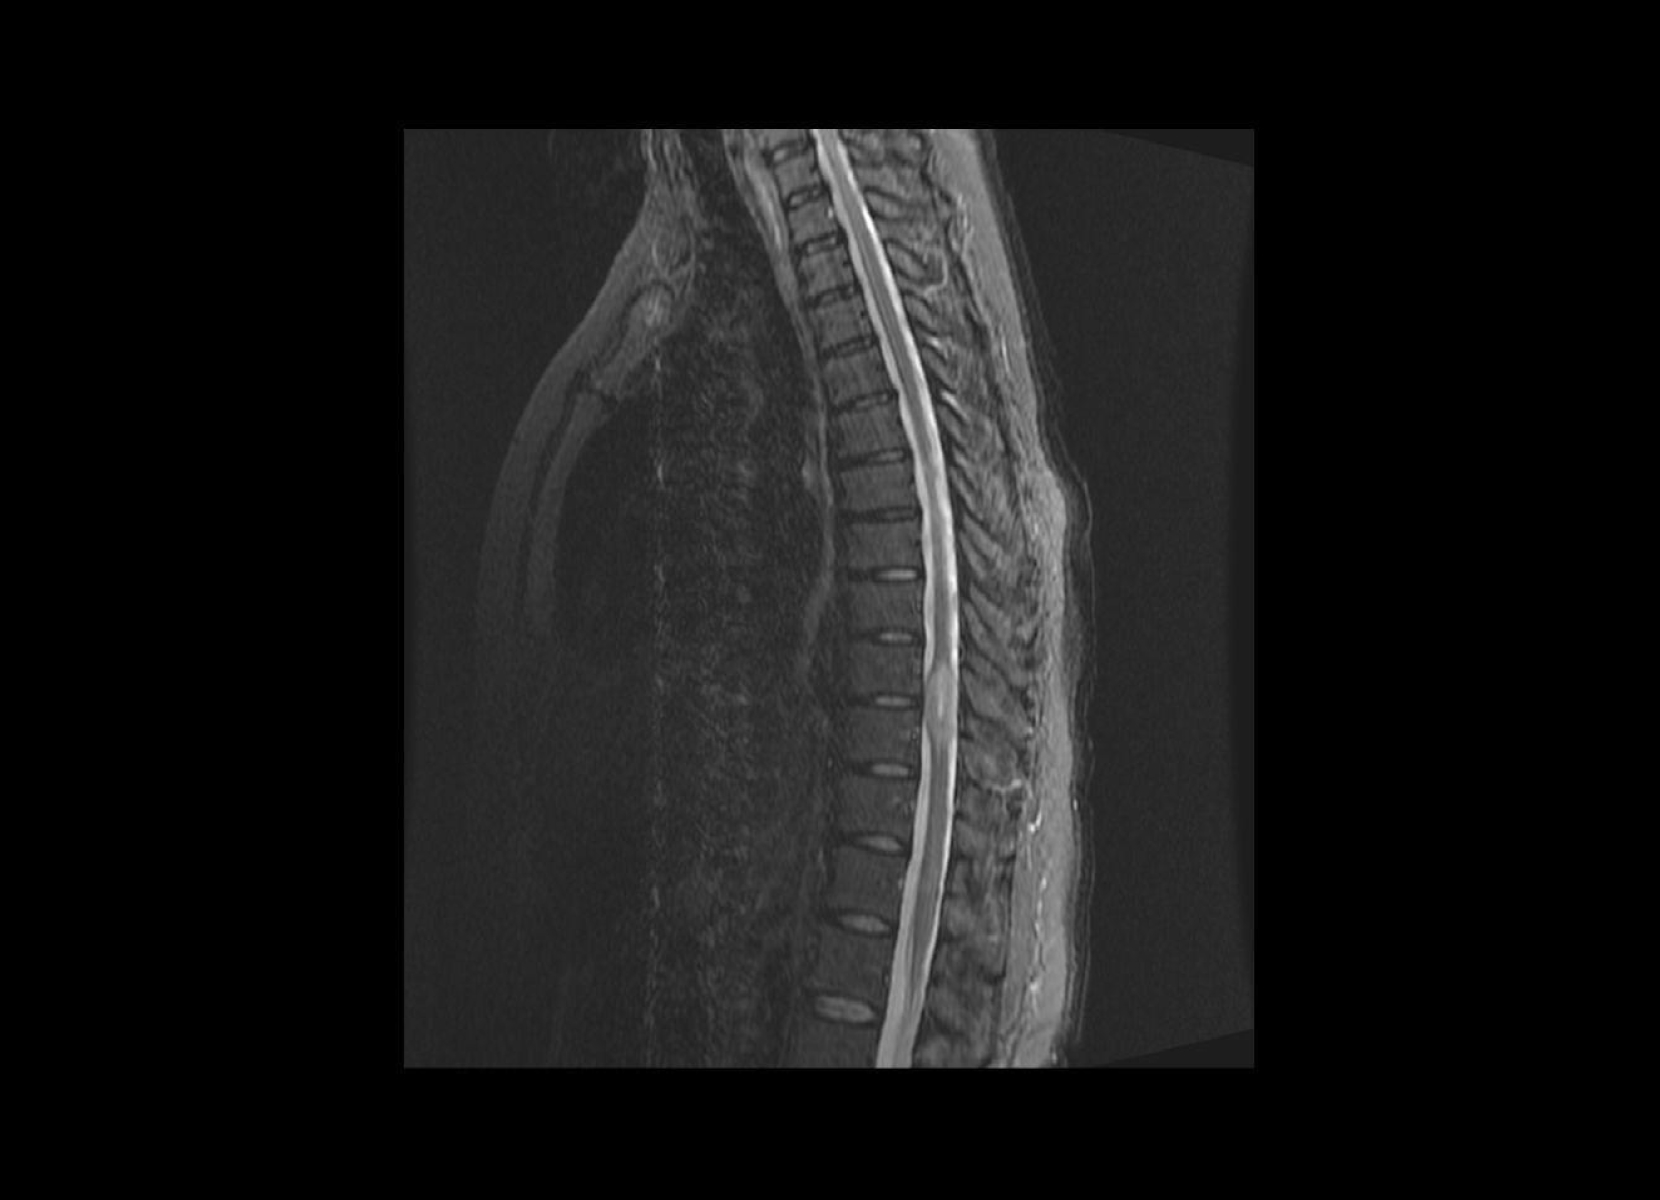

Conventional

STIR

SubtleSYNTH™

(Synthesized STIR)™

Normal

GE 1.5T

C-spine